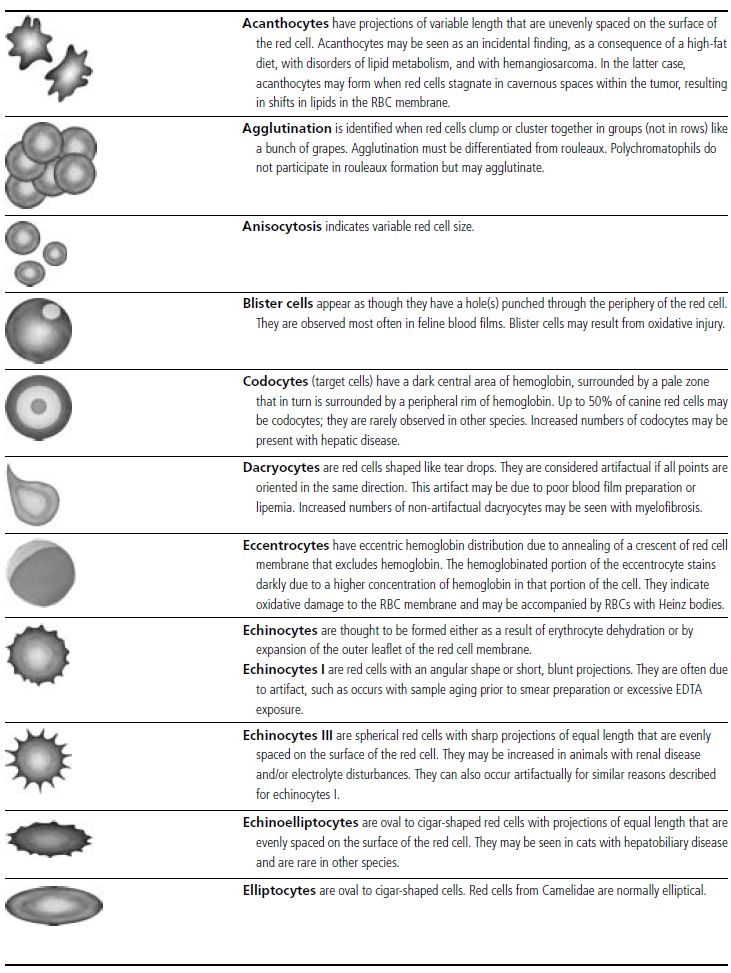

In the common domestic animals, mature erythrocytes are biconcave disks that are highly deformable, allowing them to travel through small capillaries and deliver oxygen to tissues (see Table 1.1). Erythrocyte aging and certain pathological conditions can cause RBCs to assume unusual shapes, which may result in increased rigidity. Rigid RBCs are susceptible to mechanical injury and are less effective in delivering oxygen. Exposure to stagnant environments (pooling of blood in a cavernous, hypoxic space), certain serum biochemical abnormalities, antibody-mediated membrane injury, and mechanical injury can alter the normal biconcave shape. Sometimes, RBC morphologic changes are associated with specific diseases or conditions, but the mechanism of the shape change is not clear (see Table 1.1 for diagrams of various types of RBC morphology).

See Figs 1.3–1.24 for pictures of various types of RBC morphology.

Table 1.1 Erythrocyte morphology